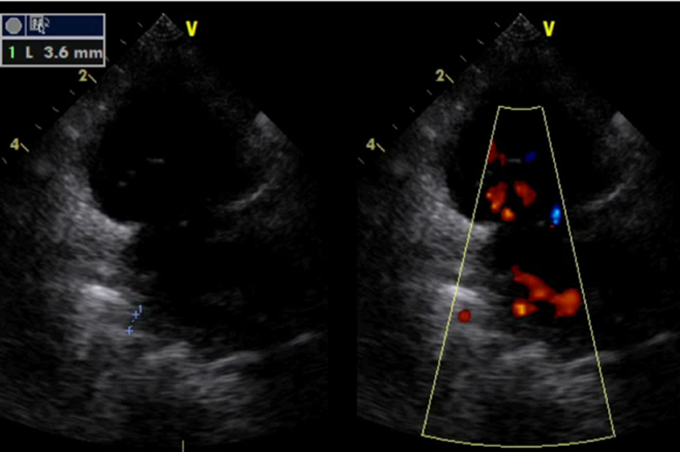

Fig. 2 Image of echocardiography

(A) Image of echocardiography before Fontan procedure. Moderate common atrioventricular valve regurgitation was observed. (B) Image of echocardiography after Fontan procedure pulmonary vein stenosis repair and common atrioventricular valve plasty. Common atrioventricular valve regurgitation was improved.

術後経過は良好で術後26日の心臓超音波検査では右下肺静脈の径は3.6 mm(Fig. 3)で,房室弁閉鎖不全は改善した(Fig. 2B).術後28日の胸部レントゲンで右肺うっ血なくCTR 41%であった.術後35日に退院した.

Fig. 3 Image of echocardiography after Fontan procedure pulmonary vein stenosis repair and common atrioventricular valve plasty

The rt lower pulmonary vein diameter was 3.6 mm and no blood flow acceleration was observed.